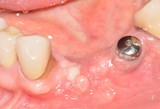

BRONJ - IV quadrante

Stadio 3